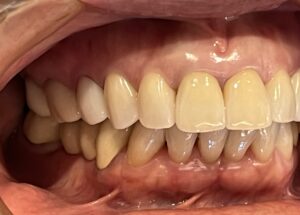

メンテナンスでいつもお越しいただいている長年の患者様が、

「前歯をもう少し綺麗になおしたい」「歯茎との境が黒くなっているのが気になる」とのことで、

仕事や生活の都合上、タイミングがあったので今回審美治療をスタートすることにしました!

元々、上の前歯に入っている補綴物の状態がこちらです。

歯と歯茎の境が黒くなっているのがわかります。

まずは元々入っている補綴物を外し、仮の歯を入れていきます。

仮歯を入れた状態がこちらです。

歯科治療において、仮歯の役割はとても重要になります。

嚙み合わせの状態や、審美的な見た目など、

仮歯の段階で何かしらのエラーに気づくことができれば事前に修正することができます。

歯肉が安定してきたら、最終の補綴物を入れる前に

天然の歯にホワイトニングをかけていきました。

白くなった歯に合わせて最終の補綴物を入れていきます。

そして前歯にフルジルコニアセラミッククラウンを入れた状態がこちらです。

Before After

歯と歯茎の境もなくしっかりとフィットし、綺麗な仕上がりになりました。

笑顔もとても素敵ですね♪